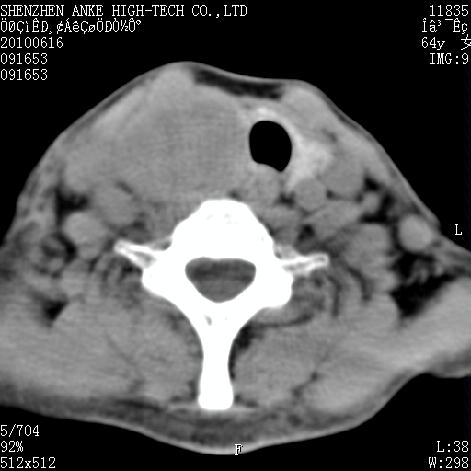

标题: CT27132:患者女,64岁,颈部及全身多处包块,现觉吞咽困难4 [打印本页]

标题: CT27132:患者女,64岁,颈部及全身多处包块,现觉吞咽困难4

右侧甲状腺占位,肿瘤可能性大,癌

右侧甲状腺癌伴右颌下腺淋巴结转移

右侧甲状腺癌伴淋巴结转移

右侧甲状腺癌伴淋巴结转移可能性大

右侧甲状腺癌伴淋巴结转移可能性大。

右侧甲状腺癌伴右颌下腺淋巴结转移!建议增强!